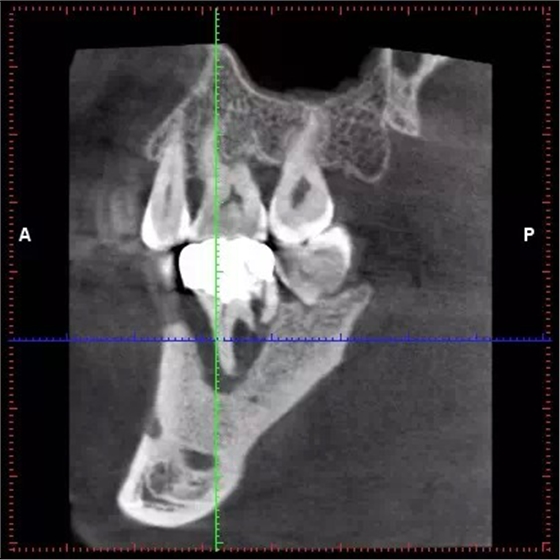

影像

CBCT診斷牙周病變結(jié)果可靠

QQ圖片20150711104326.png

土耳其一項(xiàng)研究顯示,體素值0.150 mm3被認(rèn)定為診斷牙周病變的臨界值;在牙周病變的診斷中,錐形束CT(CBCT)可被考慮為最可靠的影像學(xué)檢查模式。該論文4月22日在線發(fā)表于《口腔頜面放射學(xué)》(Dentomaxillofac Radiol)雜志。

該研究使用了12副帶有上下頜骨的顱骨。研究者使用銼刀分別在前牙、前磨牙和磨牙部位仿造牙周病變(骨開(kāi)裂、竇道、骨開(kāi)窗)。在本研究中,共有14例骨開(kāi)裂、13例骨開(kāi)窗、8例竇道患牙以及16例無(wú)牙周病變牙作為對(duì)照組。研究者使用兩臺(tái)不同機(jī)型的CBCT,獲得了在6種體素條件下(0.080、0.100、0.125、0.150、0.160、0.200 立方毫米體素值)的影像。使用Kappa系數(shù)評(píng)估在不同影像條件下的研究者組內(nèi)及組間一致性。

結(jié)果為,在0.080立方毫米體素值下的影像總體組內(nèi)Kappa值為0.978~0.973;0.160 立方毫米體素值下為0.751~0.737,該結(jié)果表明在診斷牙周病變上,上述兩種情況下具有較高的研究者組內(nèi)一致性。CBCT診斷骨開(kāi)窗準(zhǔn)確性要顯著優(yōu)于診斷竇道及骨開(kāi)裂(P<0.05)。而骨開(kāi)裂與竇道的診斷準(zhǔn)確性相比則沒(méi)有顯著差異(P>0.05)。(馬若晗 編譯)